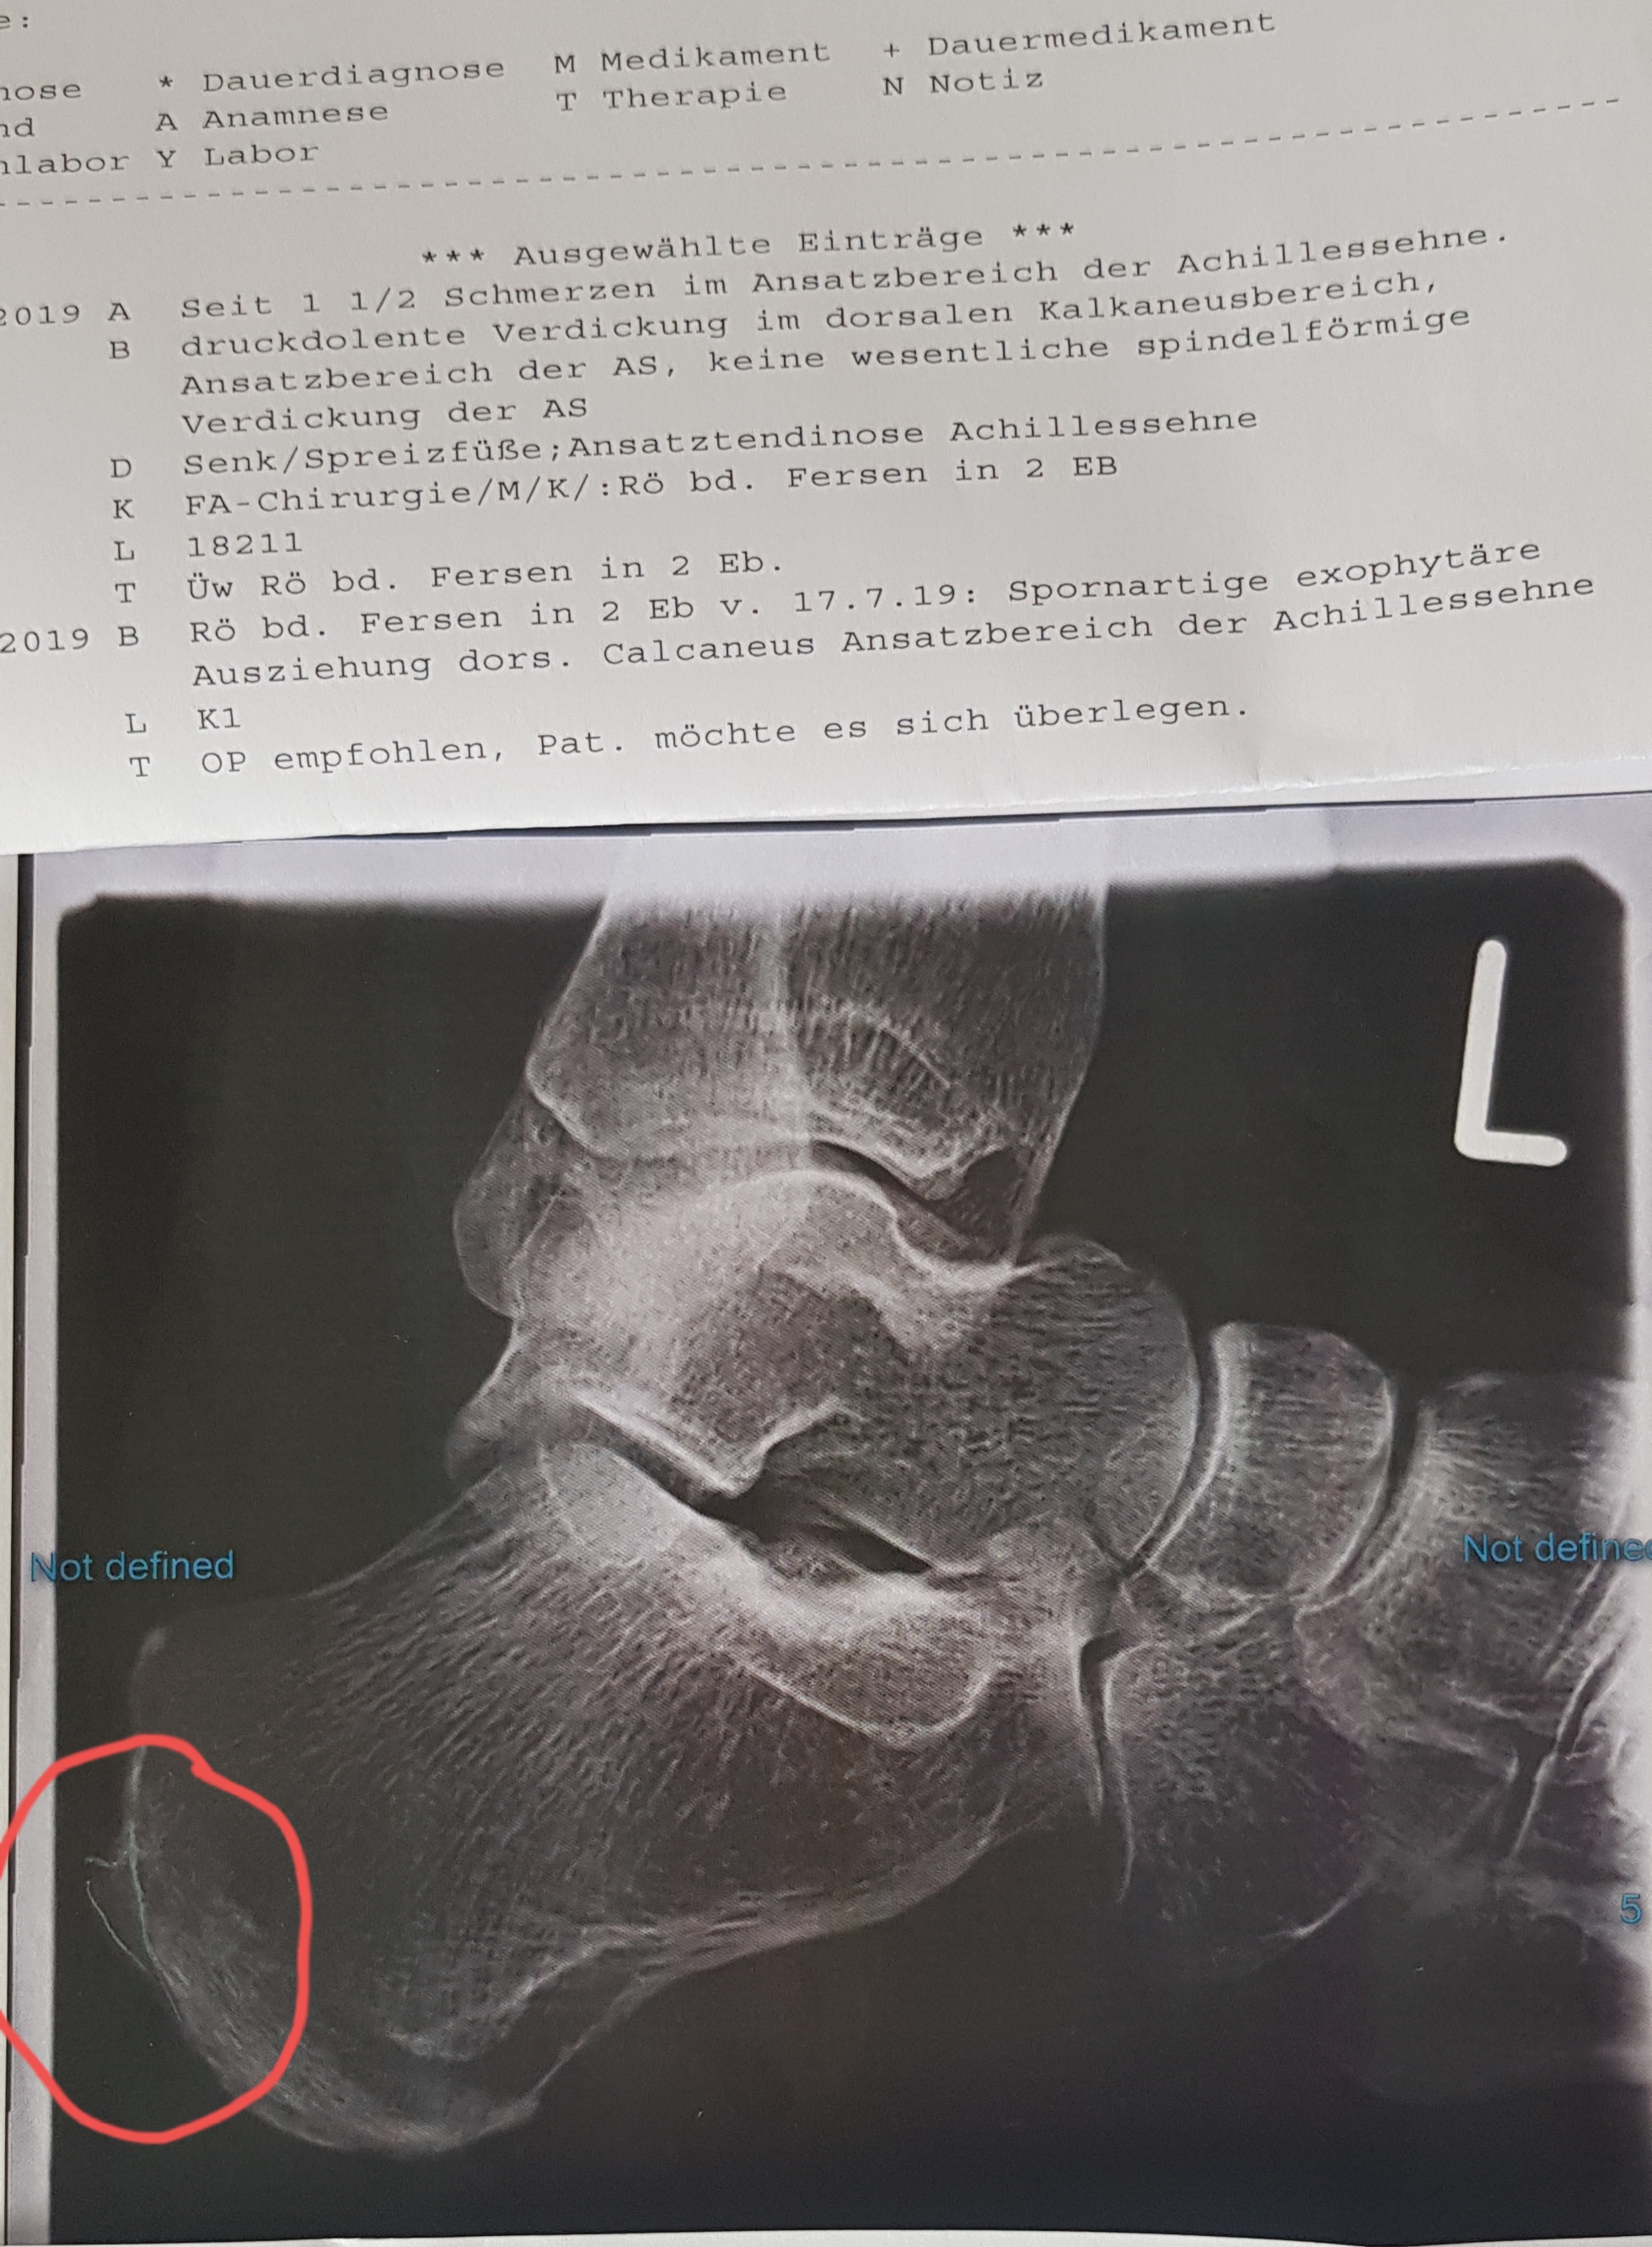

Ich habe folgende Diagnose gestern vom Orthopäden bekommen (siehe Bild und Diagnose über Bild stehend).

Ich habe so verstanden, dass durch die Zugkraft der Achillessehnen diese Wölbung an BEIDEN Fersen entstanden ist.

Er meinte das könnte man nur operativ entfernen, was aber nicht ganz ohne ist, weil ja da die Achillessehnen in die Ferse mündet. Kommt wohl auch nicht so oft vor.

Angefangen haben die Beschwerden vor anderthalb Jahren